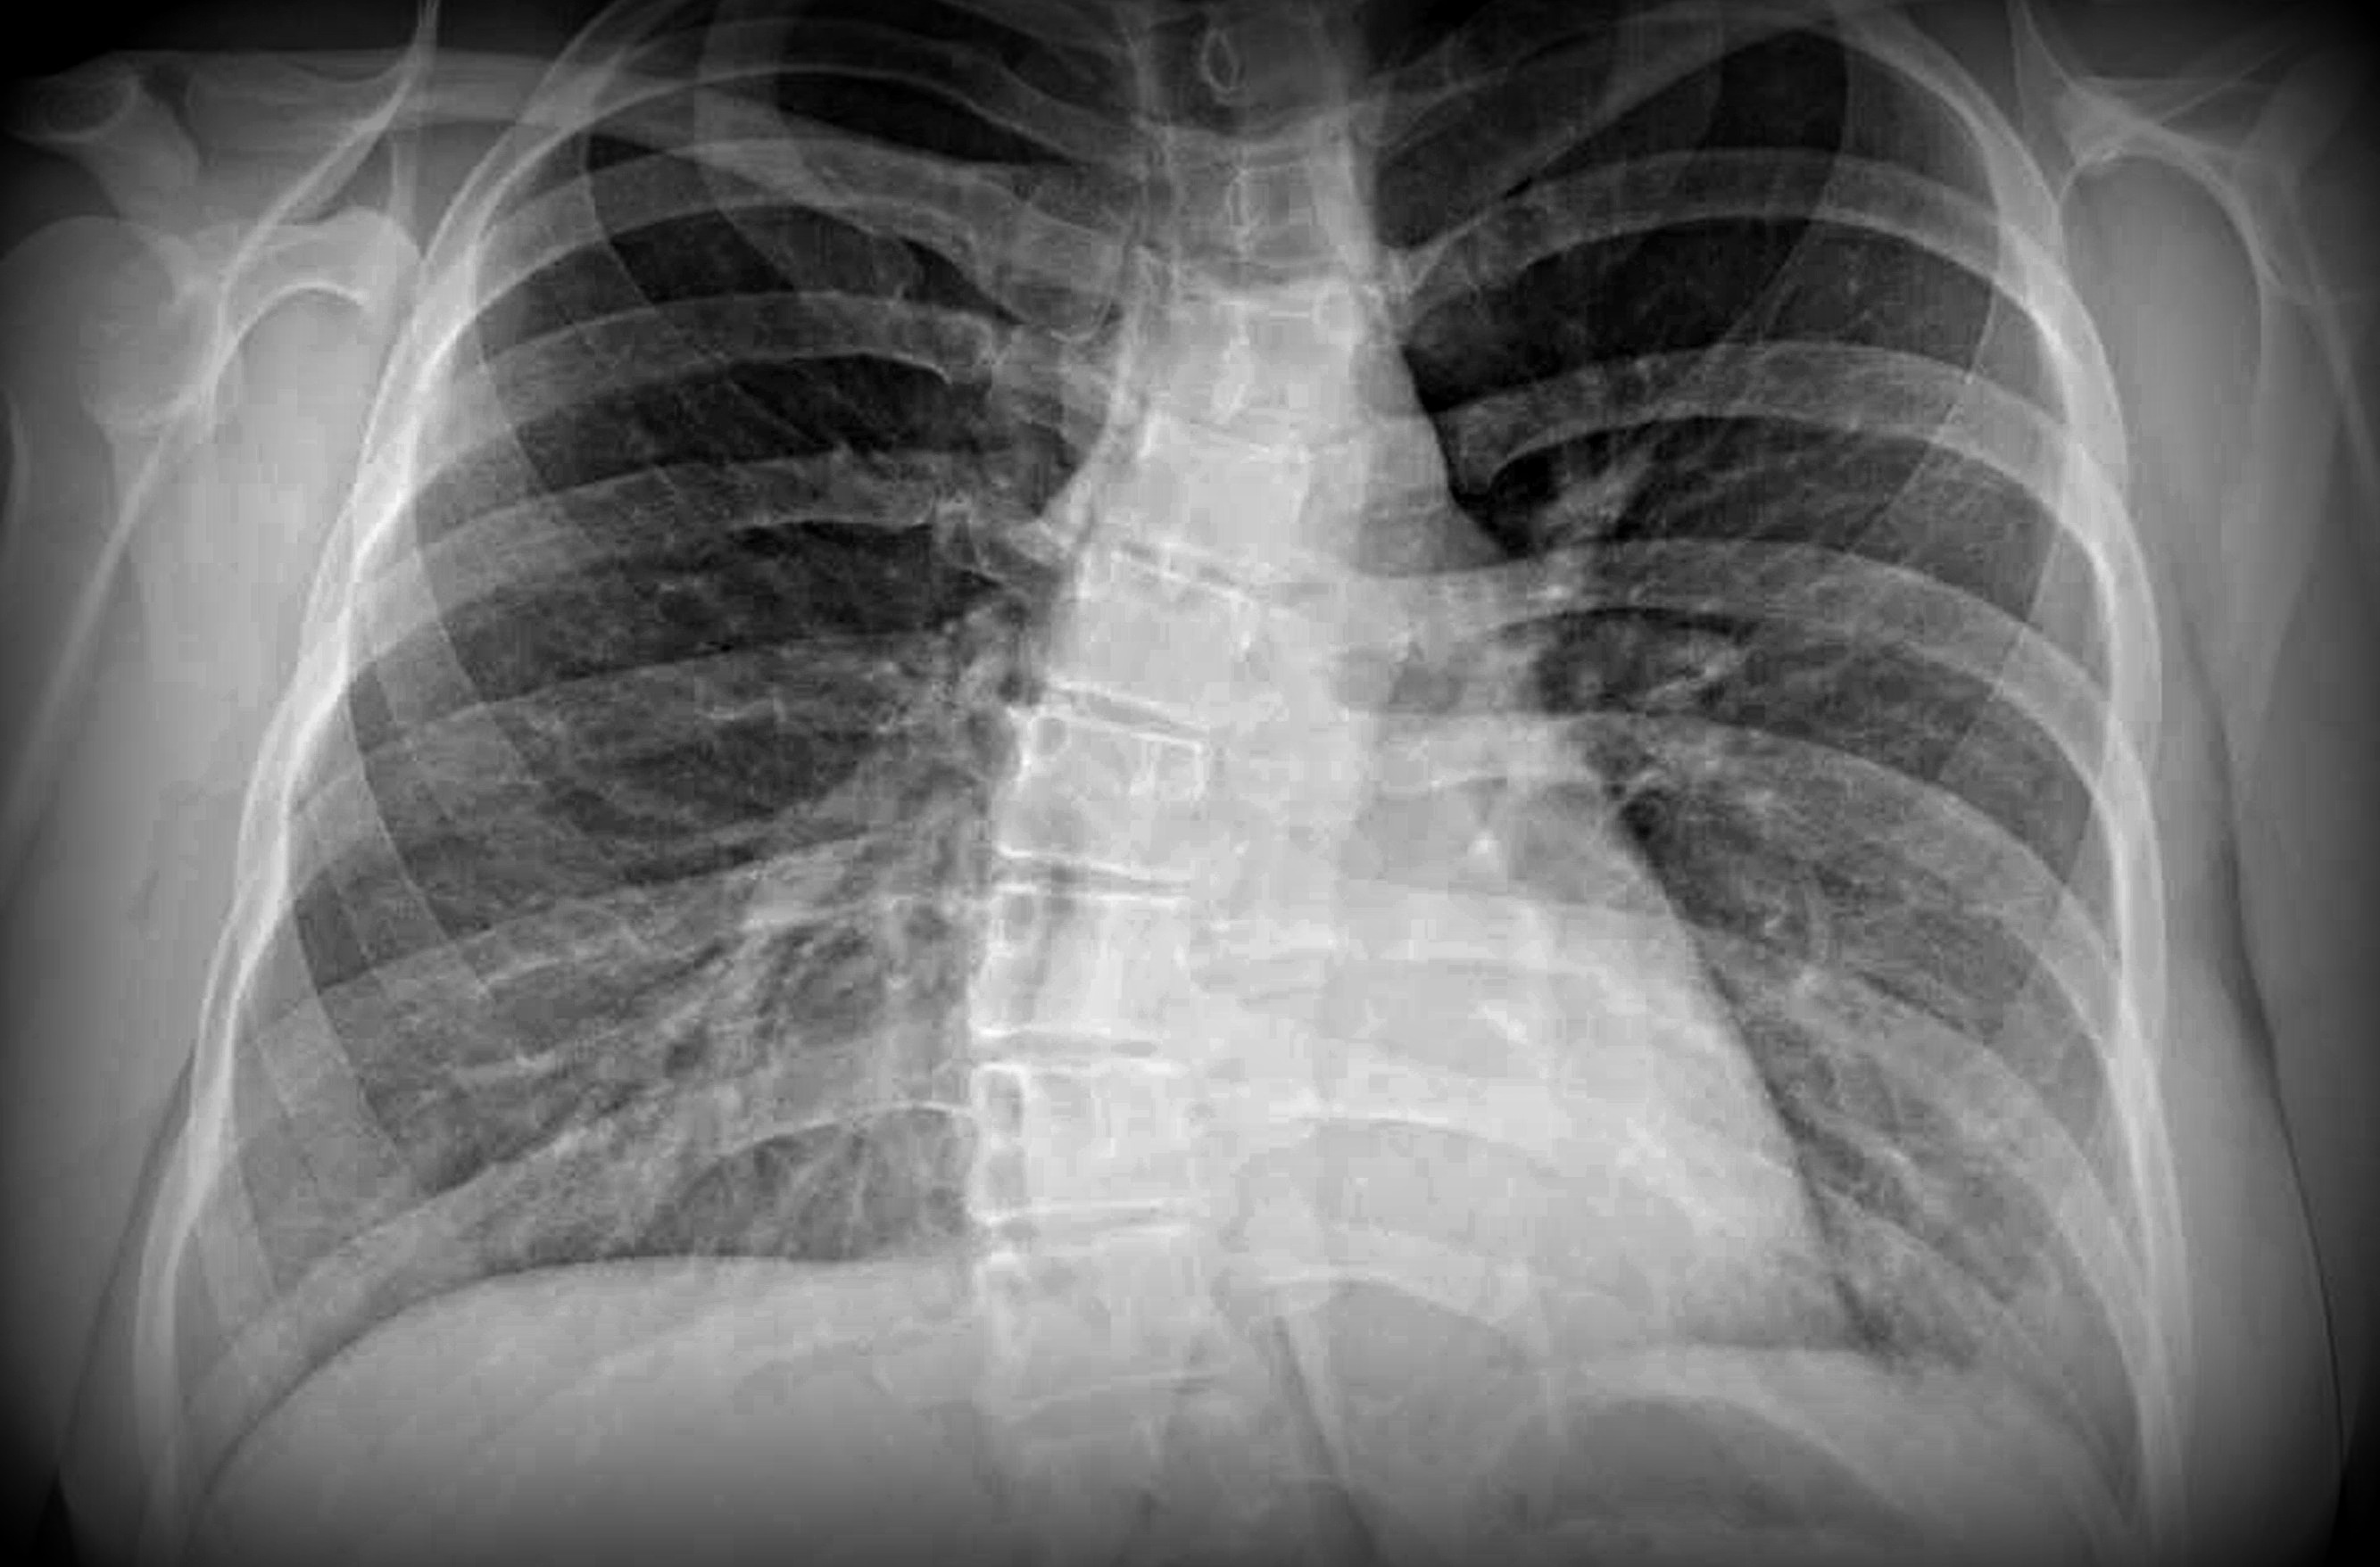

Scoliosis is a condition characterized by “a sideways curve of the spine, or backbone.”2 This curvature is typically in the shape of a “C” or “S” and can usually be diagnosed based on a person’s family history, conducting a physical examination, and X-rays of the spine.